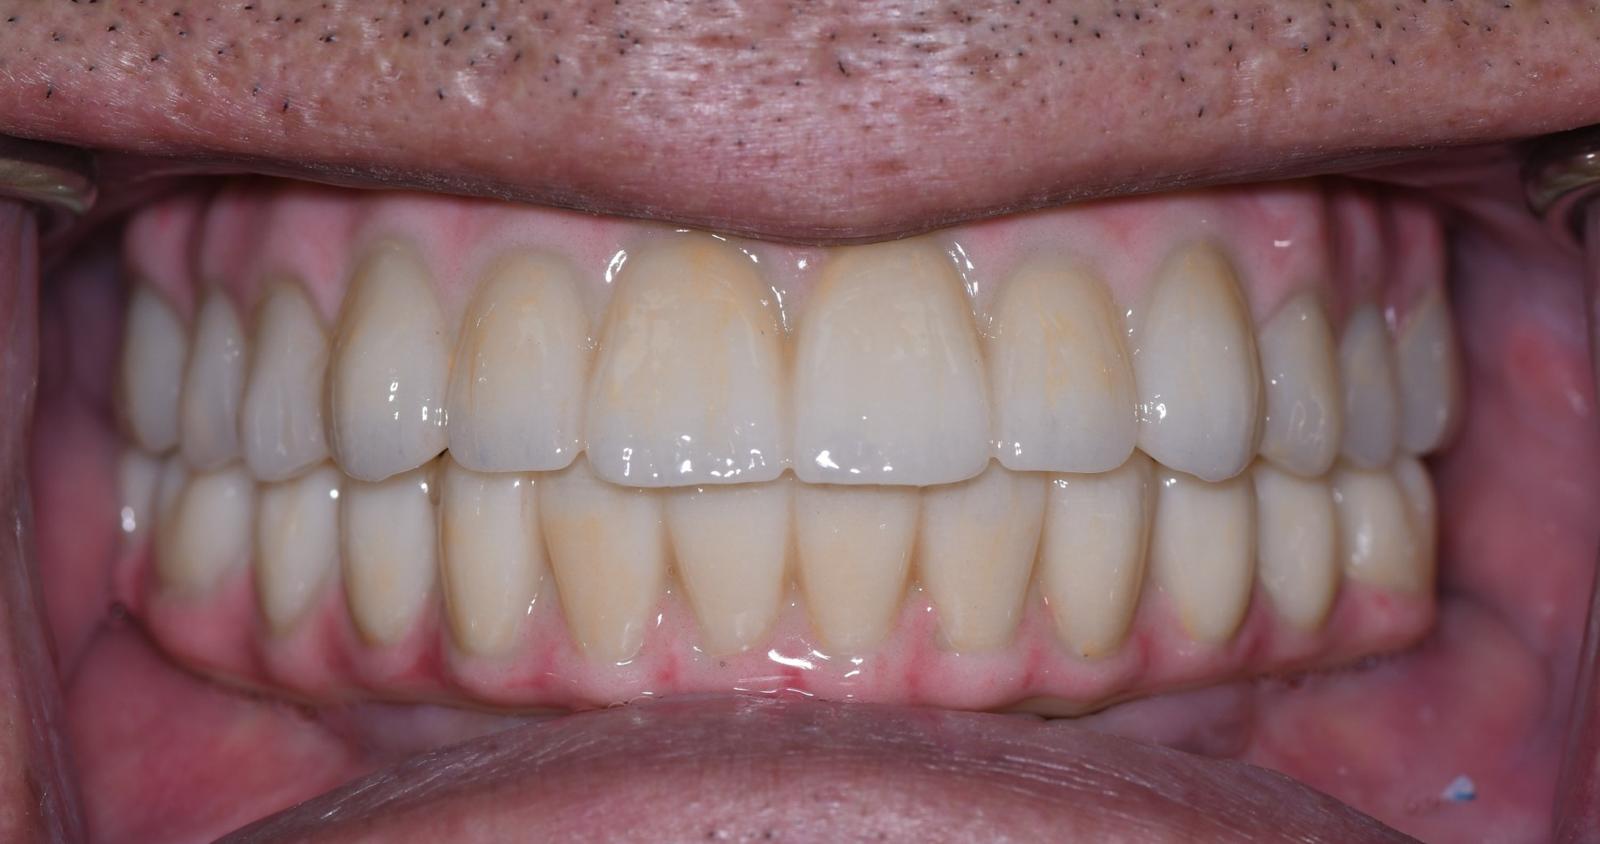

The revolutionary All-on-X (AOX) model-less workflow has become a reality through seamless integration of state-of-the-art technologies: interactive implant planning software, guided surgery systems, intraoral scanning (IOS), advanced 3D printing, and photogrammetry. Our innovative CAD-CAM protocols dramatically streamline the treatment process, reducing appointment frequency, chair time, and prosthetic delivery intervals. We've pioneered multiple digital workflows that ensure precise implant position recording and bite capture for full-arch implant rehabilitation.

The latest breakthroughs in 3D printing technology and materials enable same-day provisional restoration with unprecedented predictability. Clinicians can now consistently produce highly accurate temporaries that achieve perfect fit on multi-unit abutments (MUAs), whether using freehand or guided surgical approaches.

- Develop expertise in predictable AOX digital workflows from provisional to definitive restorations